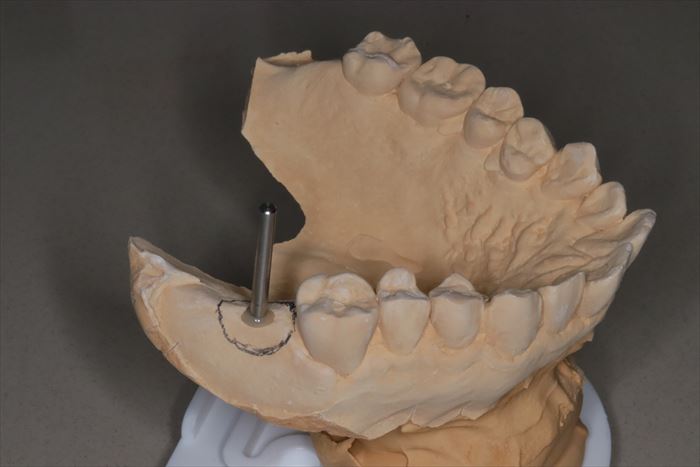

インプラントを埋入する部位を石膏模型上で確認します。

位置・角度をシミュレーションします。

サージカルステント(ドリルガイド)を作成してインプラント埋入オペに臨みます。

実際の埋入オペ時には微調整が必要であることがほとんどですので、

私は自分でシミュレーションして脳内イメージを作るようにしています。

コンピューターによるガイド作成の場合、特に第二大臼歯の場合は開口量の制限を受けて

現実には使えないケースもありますので注意が必要です。

事前準備と現場対応能力のどちらも非常に大切です。